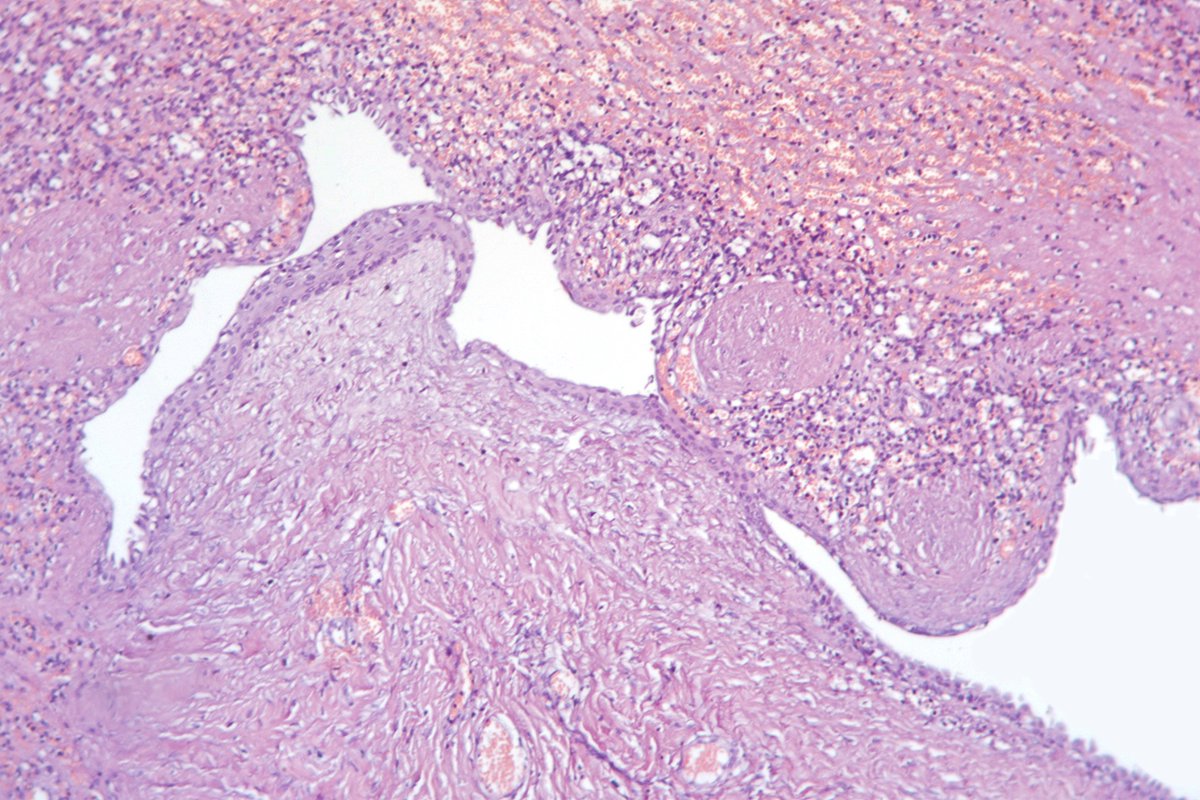

F40y,chronic cavitary pulmonary aspergillosis, atypical resection of the low lobe of the lung.

several cavities with a fungal ball, granulation tissue, chronic inflamation, metaplastic squamous epithelium, calcium oxalate crystals